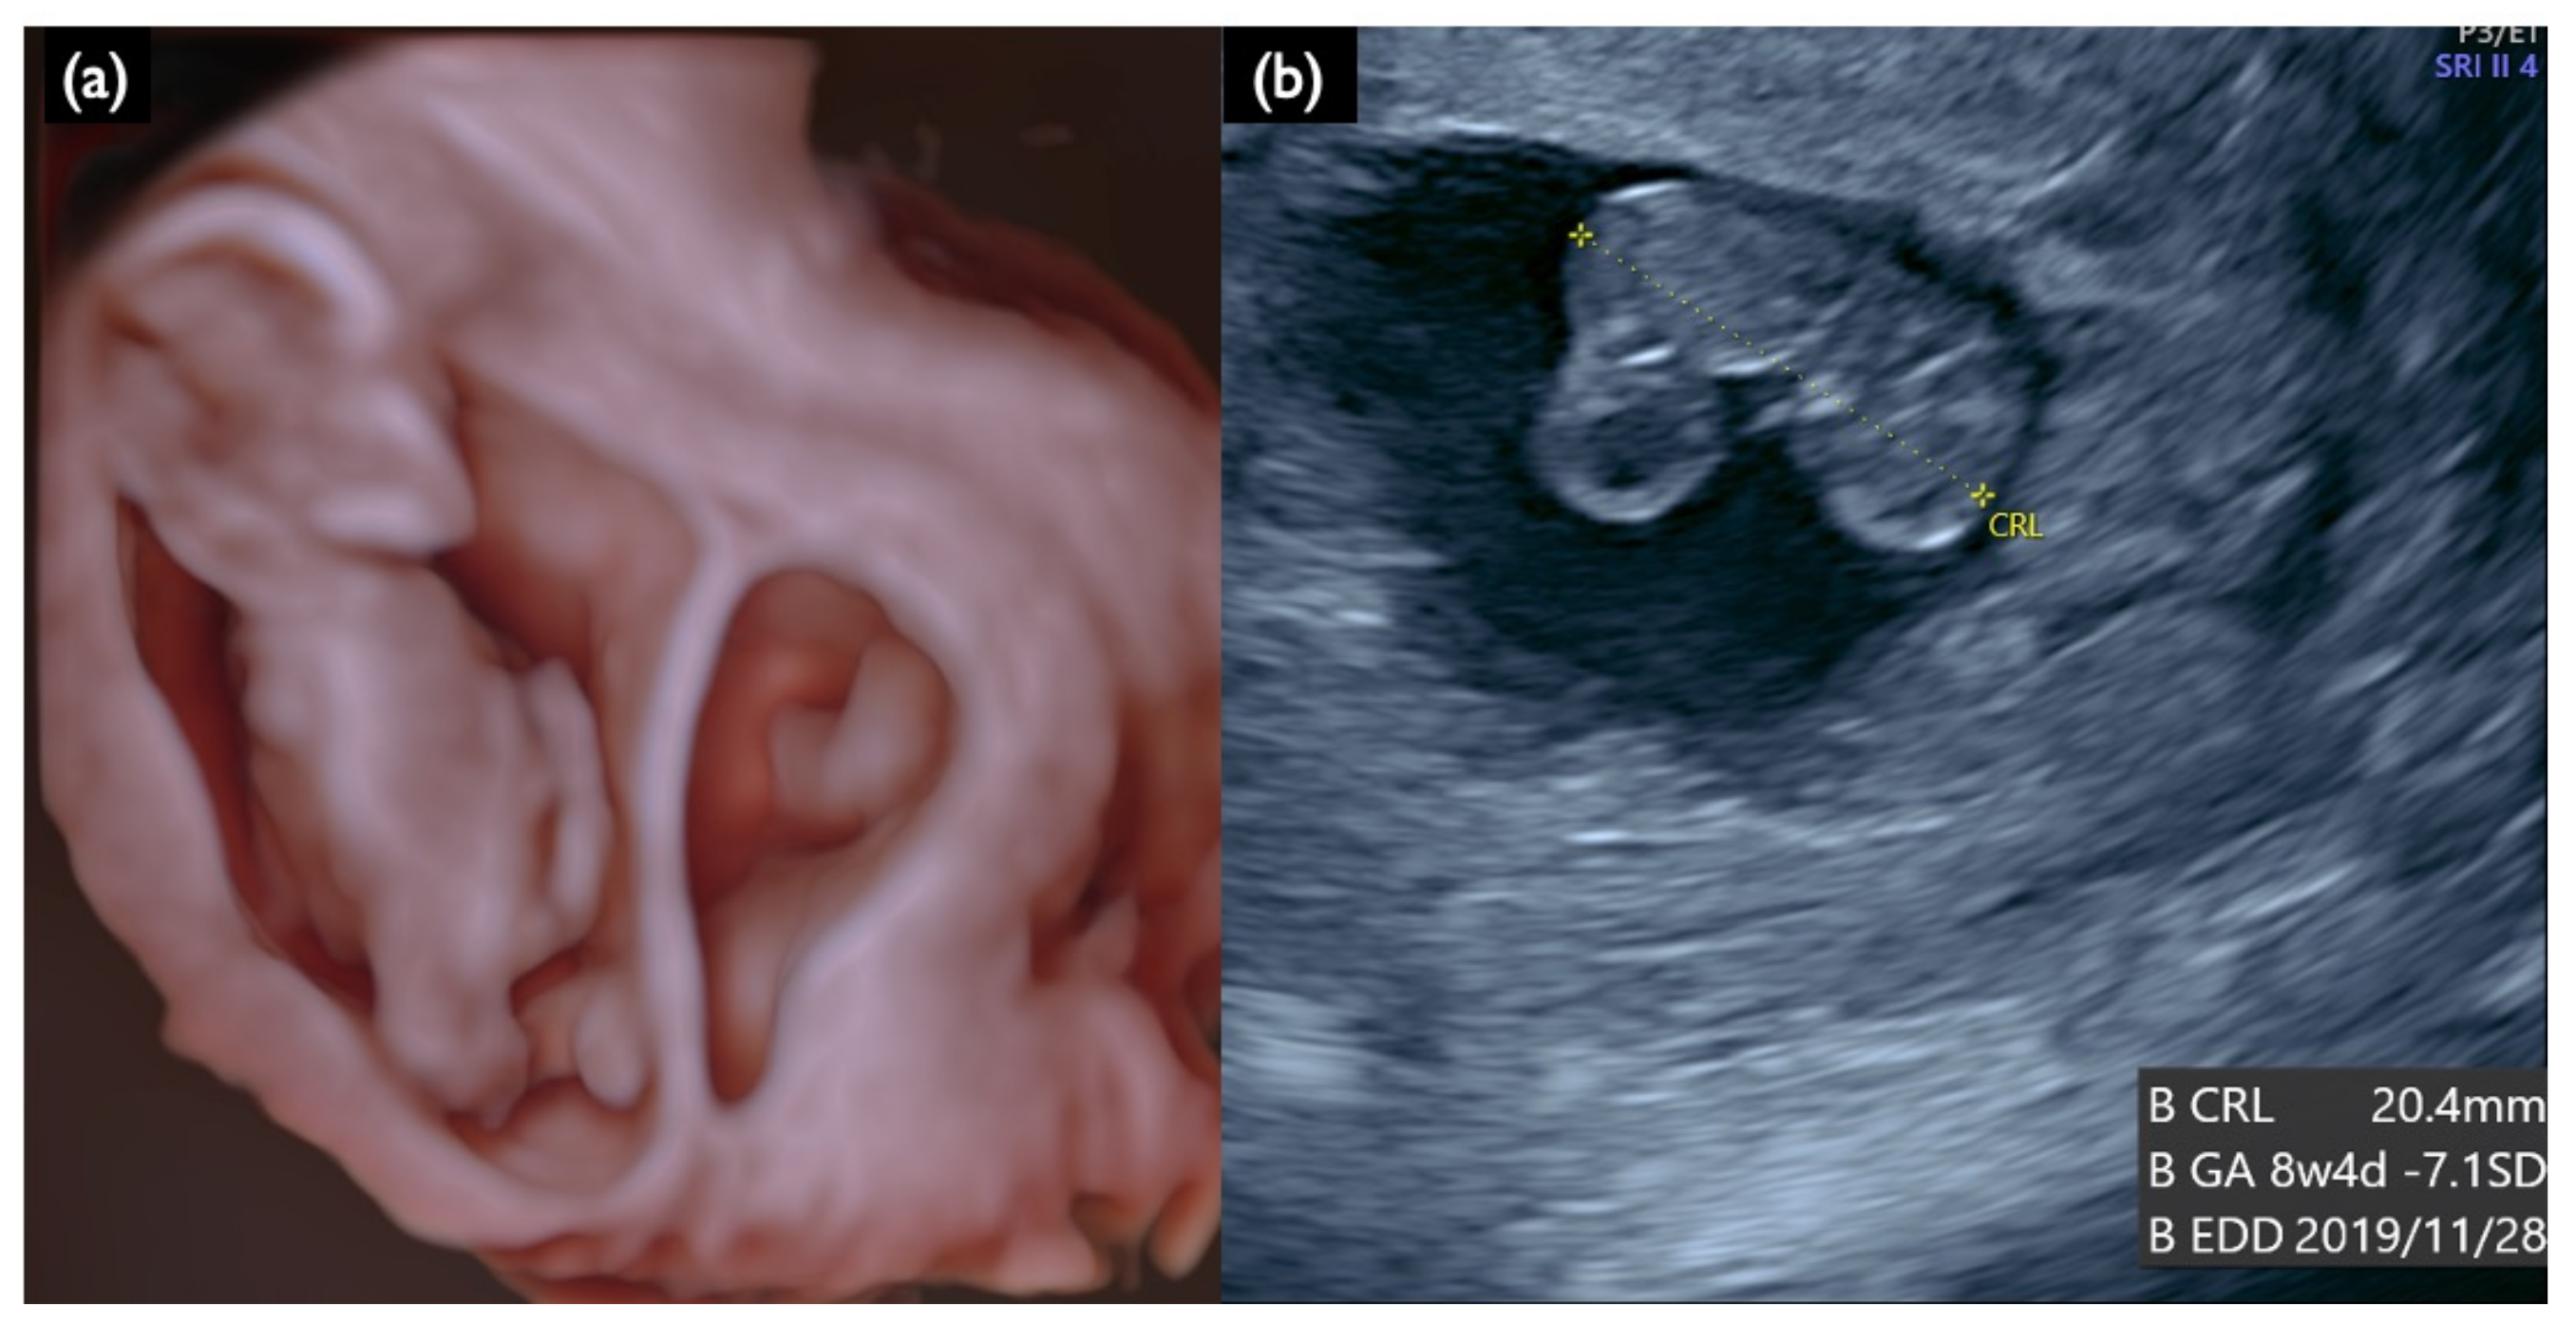

| FN1 | 47,XY,+21 | T21 negative | 1.07 | – | – | – | – | – | – | – | – | 46,XX | unclear | + | 7.2 | Increased NT, GE mild, NB defect, Lowset ear, TR mild, Small stomach, DV reverse, Tachycardia, T21 is strongly suspected |

| NC2 | 12w2d | CVS | 22.8 | 47,XY,+21 | No Call | + | 5.3 | Increased NT, Small CH, GE, bilateral, PE, NB defect, Micrognathia, Lowset ear, s/o Large VSD, TR moderate, Levocardia, RV>LV, Hyperechoic bowel, DV reverse, Short FL, T 21 is strongly suspected |

| NC3 | 13w1d | CVS | 25.8 | 47,XY,+18 | No Call | + | 10.6 | Increased NT, CH, GE, Small NB, Micrognathia, Lowset ear, Hypoplastic ear, Cleft lip (left), Maxillary gap, Mild wrist contracture bilateral, RV>LV, TR, DV reverse, Bradycardia, T18 is strongly suspected |